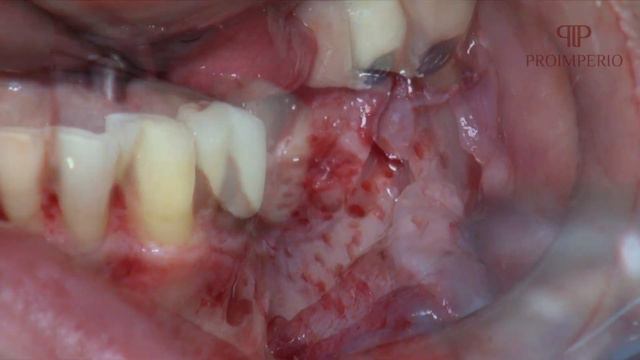

Bone Ring Posterior com Dr Marcelo Nunes - Proimperio смотреть онлайн

01:54

Bone Ring Posterior com Dr Marcelo Nunes - Proimperio